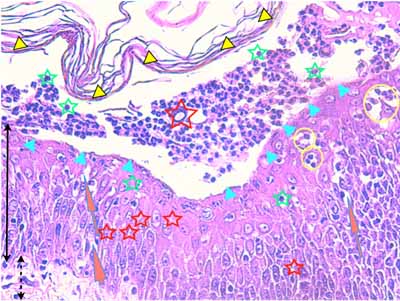

Photo 11 (Hémalun-Eosine X400) : Vue rapprochée d’une pustule intra-épidermique sous-cornée :

son toit est fragile formé de fines lamelles de kératine; son plancher épidermique

est le siège d’une forte exocytose de cellules inflammatoires; elle renferme

des granulocytes et quelques cellules épithéliales arrondies de type acantholytique.

Légendes de la Photo 11 :

- Pointes de flèche jaune : toit de la pustule intra-épidermique sous-cornée, composé de fines lamelles de kératine orthokératosique alvéolaire

- Étoile rouge évidée : cellule épithéliale acantholysée (la plus grande

- Pointes de flèche turquoise : elles délimitent le contour du plancher de la pustule intra-épidermique sous-cornée

- Flèche orange : spongiose ou œdème intercellulaire

- Étoiles vertes évidées : granulocytes dans le contenu de la pustule et en cours d’exocytose transépidermique dans le plancher épidermique

- Cercles jaunes : pustules micro-loculaires qui confluent en position sous-cornée pour former la pustule dont le plancher est matérialisé par les pointes de flèche turquoises

- Double flèche noire : épiderme

- Double flèche pointillée noire : derme